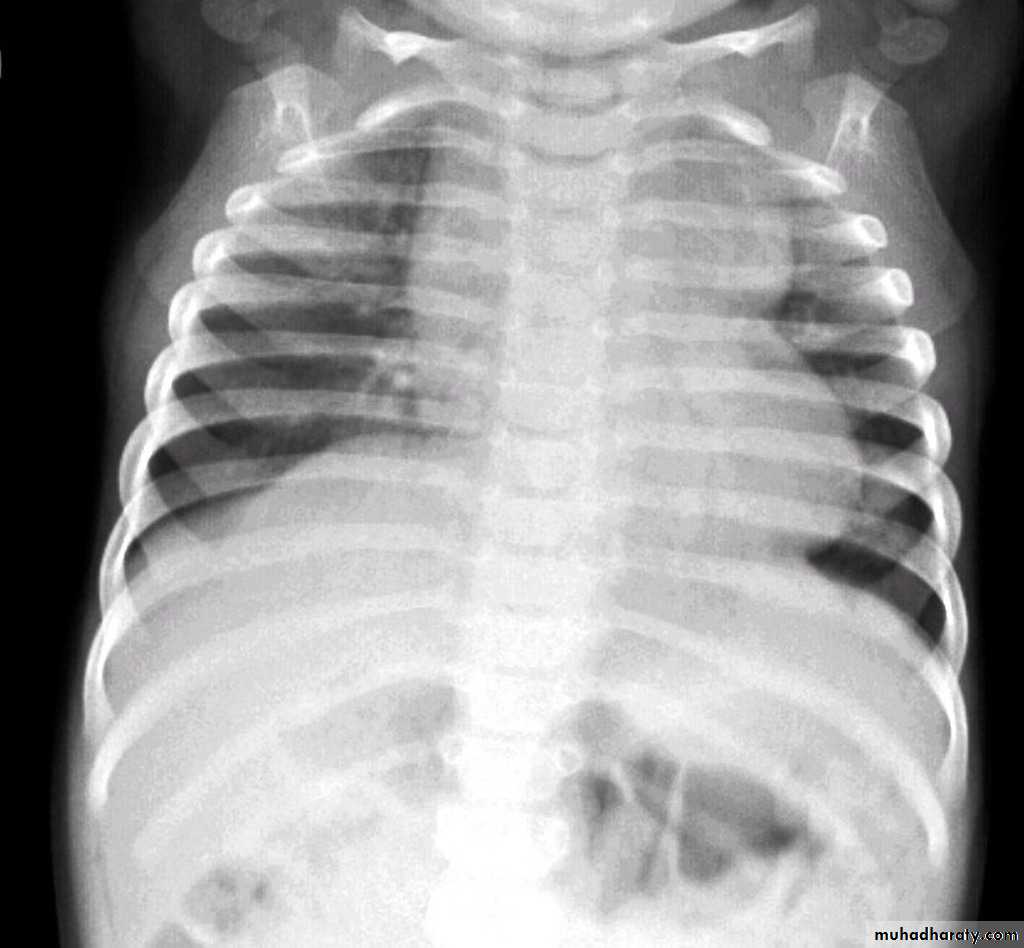

Normal thymus gland ( sail shape sign )